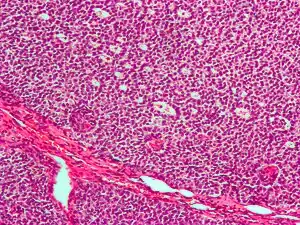

| Micrograph of a granulosa cell tumour, a type of sex-cord–gonadal stromal tumour. H&E stain. | |

Sex cord–gonadal stromal tumour is a group of tumors derived from the stromal component of the ovary and testis, which comprises the granulosa, thecal cells and fibrocytes.[1] In contrast, the epithelial cells originate from the outer epithelial lining surrounding the gonad while the germ cell tumors arise from the precursor cells of the gametes, hence the name germ cell.[1] In humans, this group accounts for 8% of ovarian cancers and under 5% of testicular cancers. Their diagnosis is histological: only a biopsy of the tumour can make an exact diagnosis. They are often suspected of being malignant prior to operation, being solid ovarian tumours that tend to occur most commonly in post menopausal women.